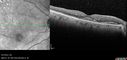

Self Sealed Retinal Arteriol Macroaneurysm468 viewsSD OCT line scan with intraretinal fluid

Self Sealed Retinal Arteriol Macroaneurysm456 viewsSD OCT line scan with intraretinal fluid